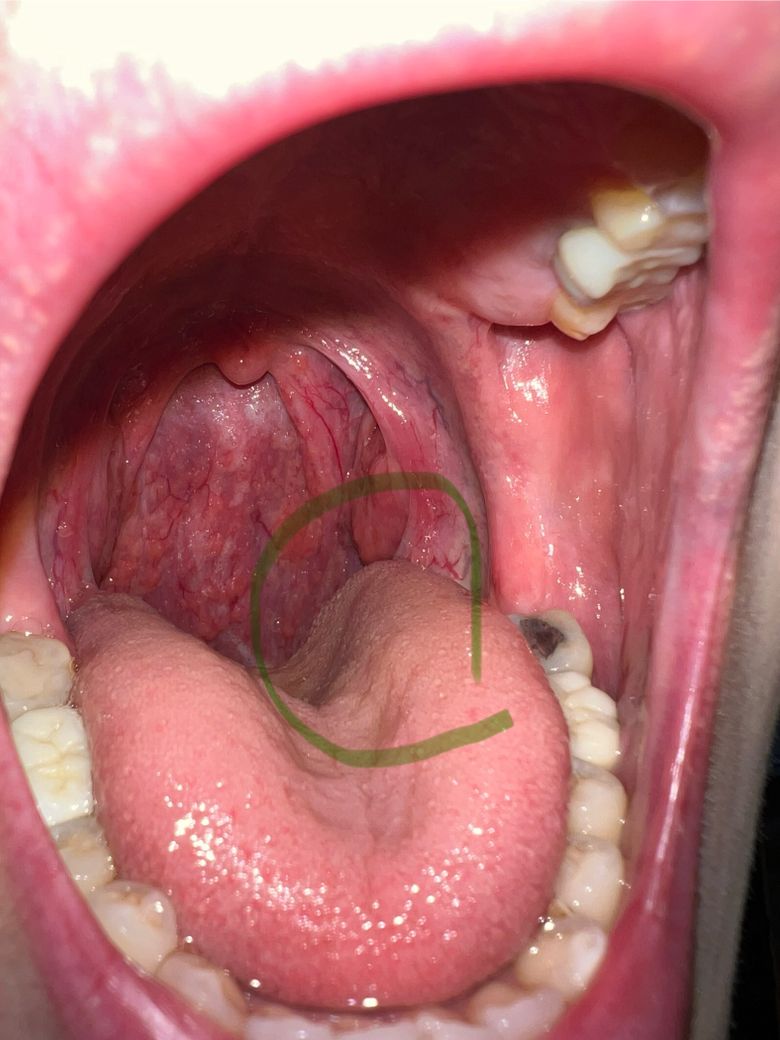

사진상 표시한 부근인데 정확한 위치는 모르겠지만 뭘 삼킬 때 이물감이 느껴져요 그거 제외하고 다른 통증이라던가 그런게 없는데 왜이런걸까요? 나이는 31살 남자고 증상은 5일정도 됐습니다. 최근 건조기를 많이 틀고잤는데 건조해서 그럴 수 있나요? 어제 이비인후과에서 가보긴 했는데 별거 없다고 가글처방만 해주시고 저는 계속 불편하고 원인이라도 알고싶네요. 혹시 편도가아니라 역류성후두염? 같은 걸수도 있나요? 만약 그렇다면 증상이 호전될 수도 있을까요?

• 1번 째 사진